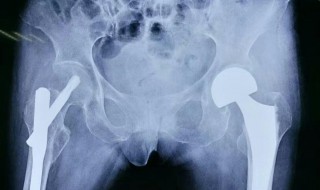

1、我们的人工骨主要指的是人工材料制造的人骨替代品或者是骨折的固定材料。人工骨的材料主要是由高分子合成材料,比如聚甲基丙烯酸甲酯,或者是高密度聚乙烯等。

2、还有一些无机材料,比如磷酸酸钙,氧化铝生物陶瓷等。建议你去当地正规医院进行手术,这样可以降低手术的风险。